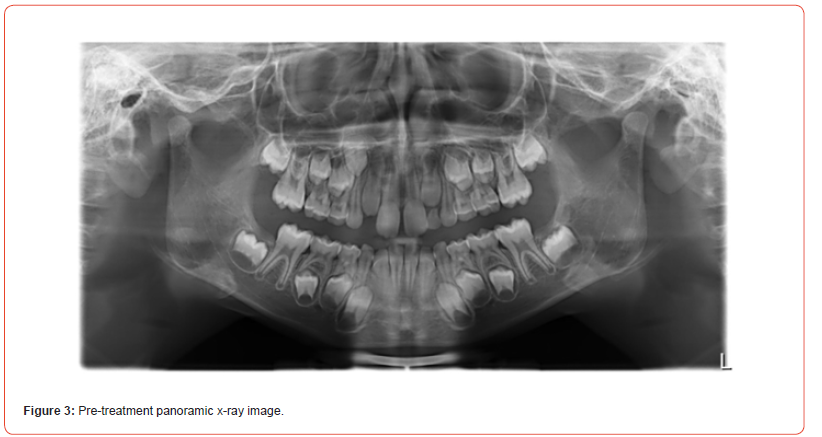

A healthy seven-year-old boy presented at the author’s orthodontic practice with a slightly convex profile, competent lips, and normal smile line (Figure 1). He had an Angle class II/1 (1/2 pw) malocclusion with a 6mm overbite and palatal contact in the early mixed dentition (Figure 2). A removable appliance was used to address the deep bite, and the first radiographic examination was done a year later and revealed the radiographic absence of the left maxillary canine (Figure 3). The decision was made to substitute the congenitally missing maxillary canine with the first maxillary premolar and use coronoplasty to avoid prosthetic replacement of the missing tooth.